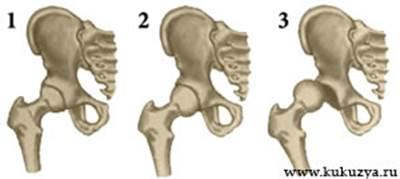

Существует 3 степени дисплазии тазобедренного сустава (врожденного вывиха бедра):

| 1 - Предвывих

2 - Подвывих

3 - Вывих

Предвывих (неустойчивость бедра)

- дисплазия I степени — недоразвитие тазобедренного сустава без смещения головки бедренной кости относительно вертлужной впадины.

Подвывих (врожденный подвывих бедра в тазобедренном суставе)

— дисплазия II степени — недоразвитие тазобедренного сустава с частичным смещением головки бедренной кости относительно вертлужной впадины.

Вывих (врожденный вывих бедра)

— дисплазия III степени — недоразвитие тазобедренного сустава с полным смещением головки бедренной кости относительно суставной впадины.